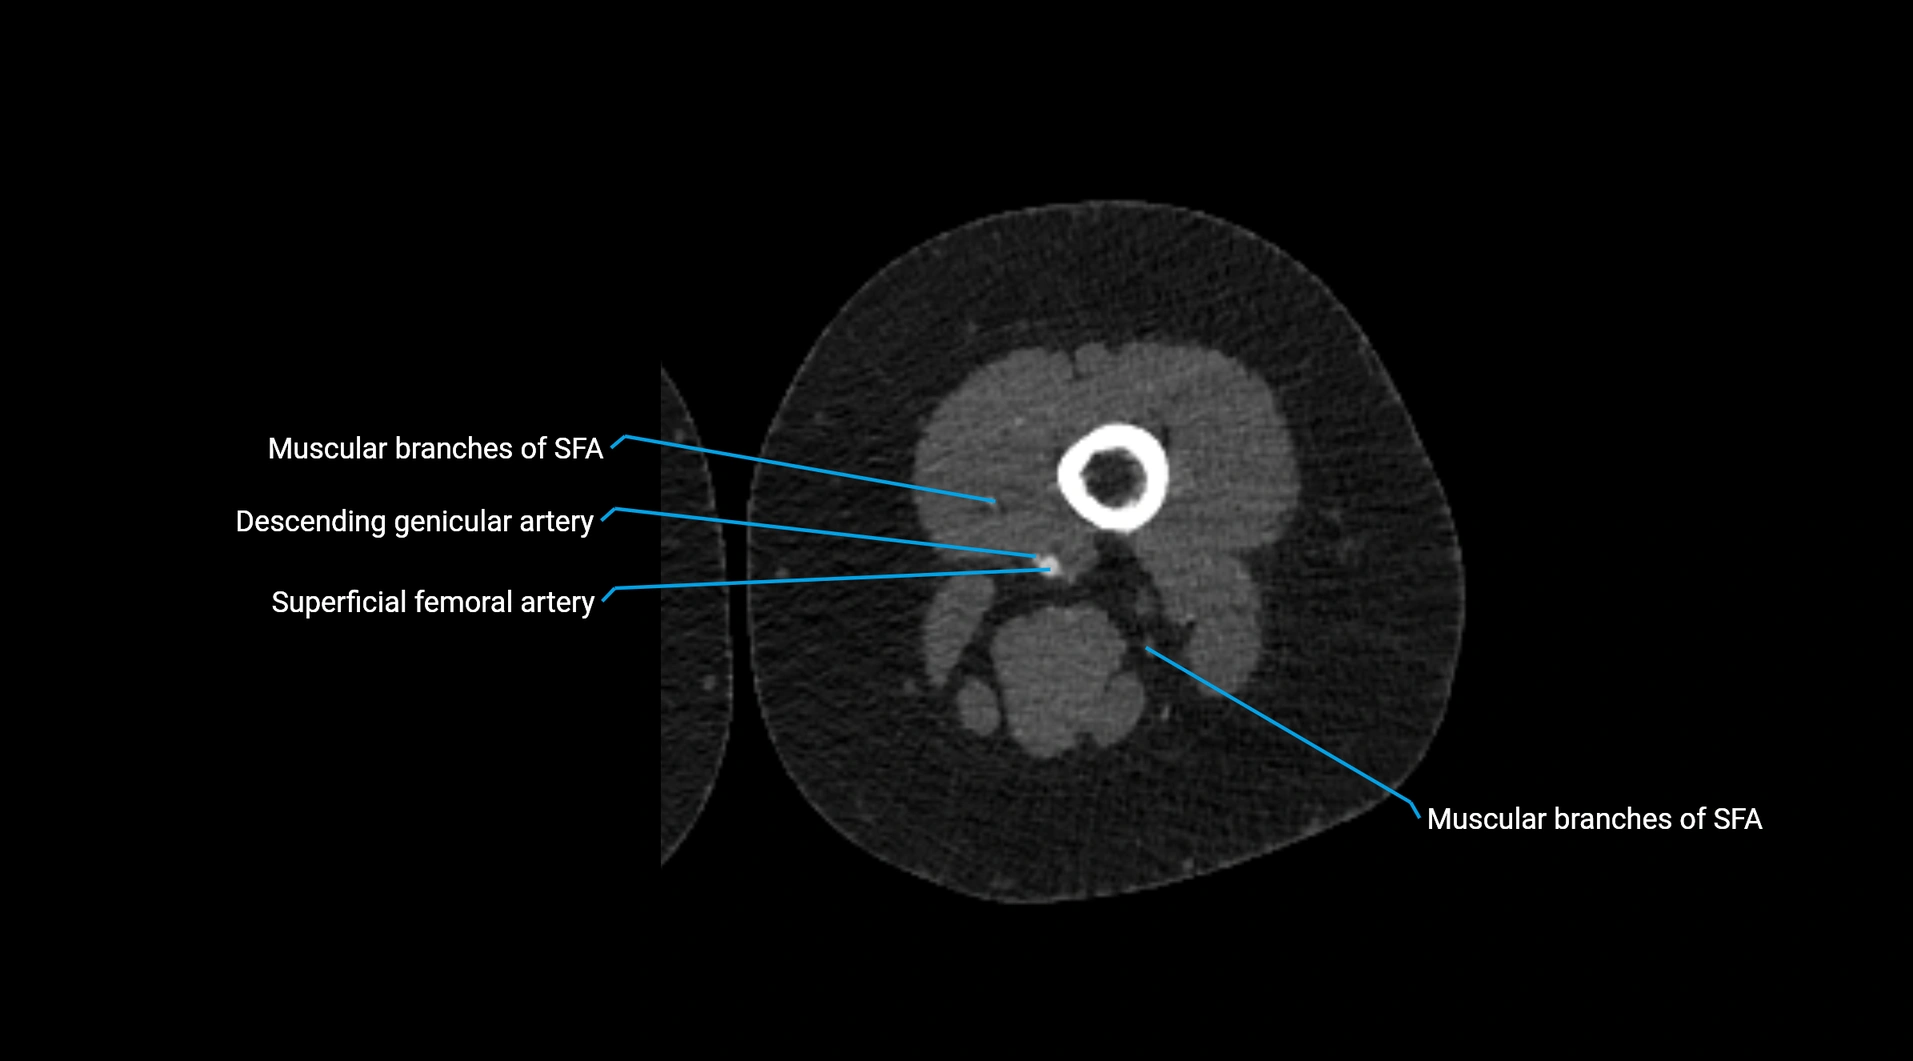

CT images

image

Contrast-enhanced CT (CTA):

• Gold standard for abdominal aortic imaging

• Provides excellent detail of lumen, wall, aneurysm, thrombus, and branch vessels

• Multiplanar and 3D reconstructions help in aneurysm measurement, stent graft planning, and dissection evaluation